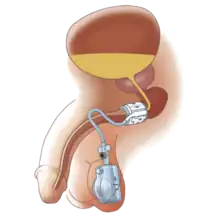

Artificial urinary sphincter

Another procedure to treat incontinence is the use of an artificial urinary sphincter, more used in men than in women. In this procedure, the surgeon enters and wraps the cuff of the artificial urinary sphincter around the urethra, in the same manner a blood pressure cuff wraps around your arm. The device includes a pump implanted under the skin that, when pressed by the patient, loosens the cuff, allowing for free urination. After that, the artificial sphincter automatically regains its pressure, closing the urethra again, and providing proper continence.[20]